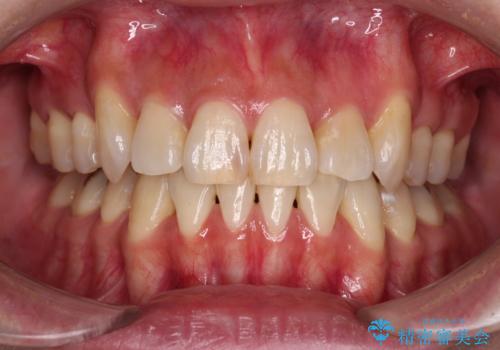

ハーフリンガルでの矯正治療は、表側矯正よりも期間がかかることが多く、抜歯矯正では3年以上かかることも珍しくありません。

デコボコが強い一方で出っ歯ではなかったため、抜歯したスペースを容易に閉じることができ、短期間での治療となりました。